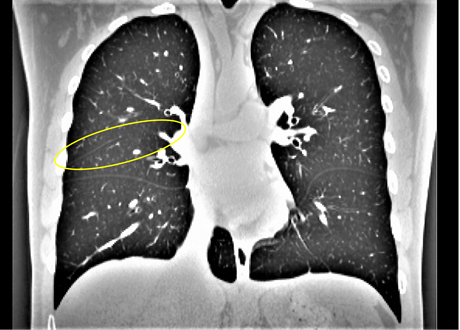

(1) Brain MR (2) Liver MR (3) Liver CT (4) Lung CT

We first introduce a method for connecting the output of a CNN to an ACM, yielding a model for the precise delineation of lesions, to which we refer as Deep Active Lesion Segmentation (DALS) (Figure 4). We then go further to introduce a truly unified framework (Figure 5) that bridges the gap between ACMs and CNNs by leveraging a novel, automatically differentiable level-set ACM with trainable parameters that allows for back-propagation of gradients and can be end-to-end trained along with a backbone CNN from scratch, without any CNN pre-training. The ACM is initialized directly by the CNN and utilizes an energy functional that is locally-tunable by the backbone CNN, through 2D feature maps. Thus, our work overcomes the big hurdle of fully automating the powerful ACM approach to image segmentation. We have applied our proposed framework to the task of building segmentation in aerial images (Figure 6).

Deep Active Lesion Segmentation

[45]: Lesion segmentation is an important problem in computer-assisted diagnosis that remains challenging due to the prevalence of low contrast, irregular boundaries that are unamenable to shape priors. We introduce Deep Active Lesion Segmentation (DALS), a fully automated segmentation framework that leverages the powerful nonlinear feature extraction abilities of FCNs and the precise boundary delineation abilities of ACMs. Our DALS framework benefits from an improved level-set ACM formulation with a per-pixel-parameterized energy functional and a novel multiscale encoder-decoder CNN that learns an initialization probability map along with parameter maps for the ACM. We evaluate our lesion segmentation model on a new Multiorgan Lesion Segmentation (MLS) dataset that contains images of various organs, including brain, liver, and lung, across different imaging modalities—MR and CT. Our results demonstrate favorable performance compared to competing methods, especially for small training datasets. -